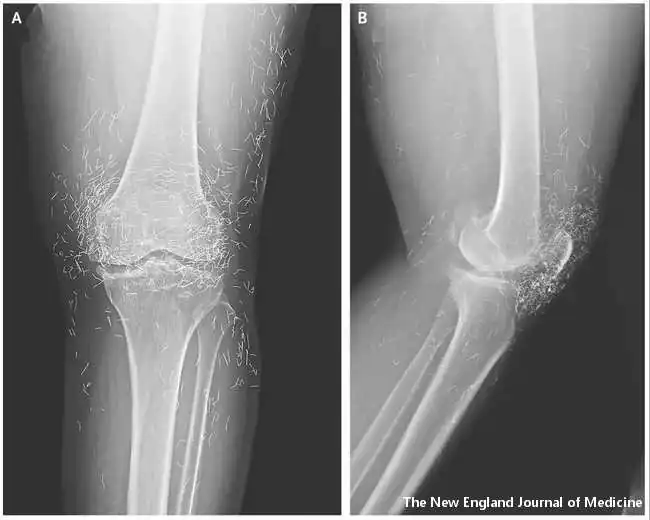

Rendgenski pregled je otkrio zadebljanje i otvrdnjavanje unutrašnjeg dela tibije, koštane izrasline u kolenu, sve uobičajene simptome osteoartritisa.

Istovremeno su lekari otkrili na stotine sitnih zlatnih niti ugrađenih u tkivo oko kolena.